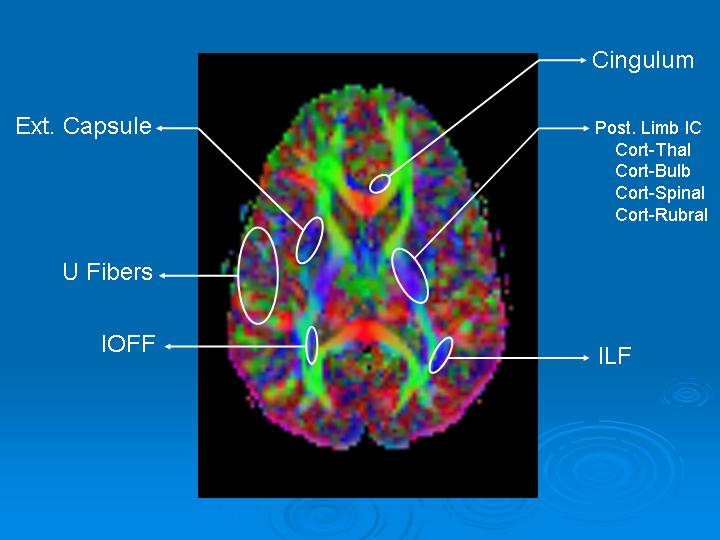

Main Cerebral Tracts on

Orthogonal Fractional Anisotropy Maps

Cerebral tracts may be presented in 2D color images in: axial, coronal, and sagittal planes. The relational topographic appearance of the tracts are better identified in planes that are perpendicular to the major axis of the tract. For example, the corpus callosum which is an axial structure is better defined in the sagittal or coronal view. Thus, tracts going anterior-posterior or posterior-anterior are better seen in coronal view. Descending and ascending tracts are better depicted in axial view (Figure 1).

Figure 1. Axial FA Map. We have targeted blue fibers which encodes for foot-head or head-foot direction.

- Ext: External.

- IC: Internal Capsule

- IOFF: Inferior Occipito-Frontal Fasciculus

- Post: Posterior

- Cort: Cortical

- Thal: Thalamic

- Bulb: Bulbar

- ILF: Inferior Longitudinal Fasciculus

Notice that the portion of the ILF and IOFF shown are just some bundles ascending in the posterior portions as these fasciculi are predominantly posterio-anterior oriented.